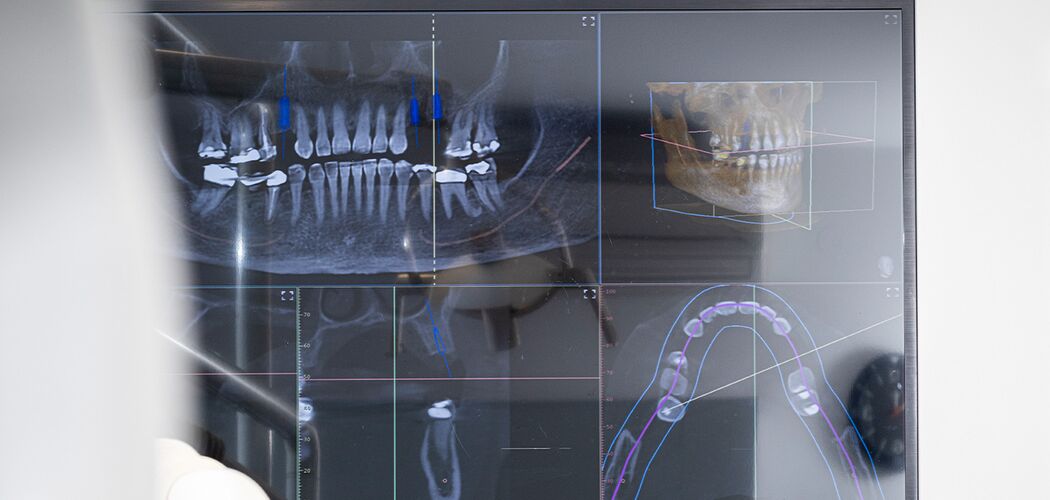

Digitales Röntgen/ DVT

Mit unserem digitalen Röntgen erhalten wir gestochen scharfe Bilder bei deutlich reduzierter Strahlenbelastung.

Für komplexe Fälle setzen wir zusätzlich auf die Digitale Volumentomographie (DVT): ein 3D-Röntgenverfahren, das Knochenstrukturen und Nervenverläufe dreidimensional sichtbar macht. Ideal für lmplantatplanung, Wurzelbehandlungen oder Kiefergelenkdiagnostik.